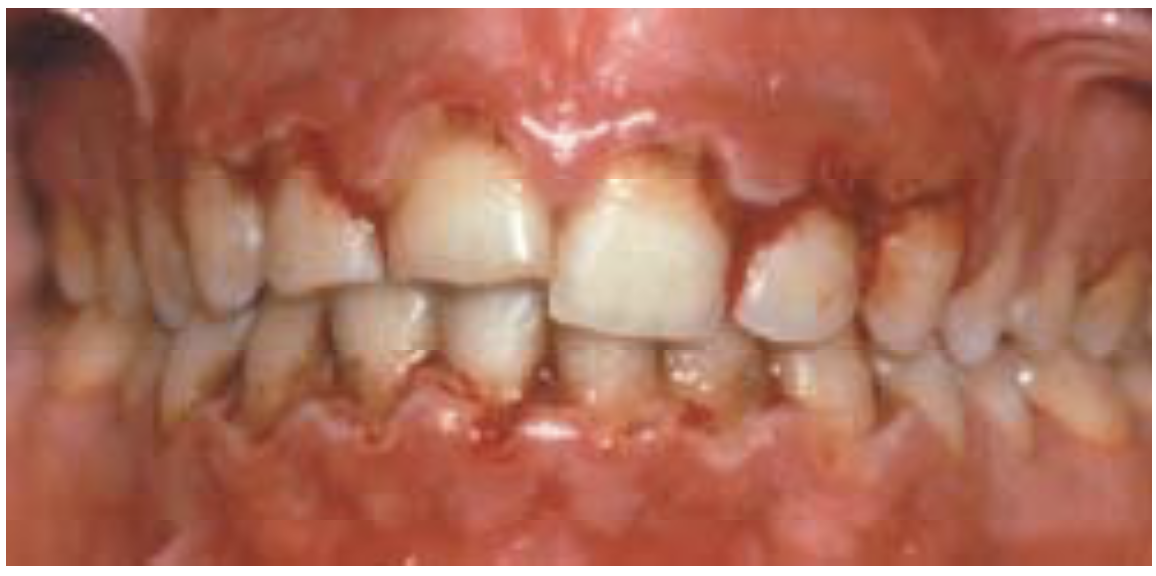

Gingivitis Necrotizante . Symptoms are acute pain, bleeding, and foul breath. Los síntomas son dolor agudo, sangrado y aliento de olor. Diagnosis is based on clinical findings. Treatment is gentle debridement, improved oral hygiene, mouth rinses, supportive care, and, if debridement must be delayed, antibiotics. La gingivitis ulcerativa necrosante aguda es una infección dolorosa de las encías. Acute necrotizing ulcerative gingivitis (anug) is a rare infectious disease of the gum tissue, affecting <1% of the population. Covers the management of acute necrotizing ulcerative gingivitis where the gums are acutely painful and swollen; The aim of this narrative literature review was to describe the available evidence on the diagnosis and treatment of ng, and present. Anug presents as an acute, painful, and destructive. They bleed easily and have. There are three major forms: It has an acute clinical presentation with the distinctive. Acute necrotizing ulcerative gingivitis is a painful infection of the gums. Necrotizing ulcerative gingivitis (nug) is a typical form of periodontal diseases.

Gingivitis Necrotizante La gingivitis ulcerativa necrosante aguda es una infección dolorosa de las encías. It has an acute clinical presentation with the distinctive. Diagnosis is based on clinical findings. They bleed easily and have. La gingivitis ulcerativa necrosante aguda es una infección dolorosa de las encías. Acute necrotizing ulcerative gingivitis is a painful infection of the gums. There are three major forms: The aim of this narrative literature review was to describe the available evidence on the diagnosis and treatment of ng, and present. Treatment is gentle debridement, improved oral hygiene, mouth rinses, supportive care, and, if debridement must be delayed, antibiotics. Anug presents as an acute, painful, and destructive. Symptoms are acute pain, bleeding, and foul breath. Covers the management of acute necrotizing ulcerative gingivitis where the gums are acutely painful and swollen; Los síntomas son dolor agudo, sangrado y aliento de olor. Necrotizing ulcerative gingivitis (nug) is a typical form of periodontal diseases. Acute necrotizing ulcerative gingivitis (anug) is a rare infectious disease of the gum tissue, affecting <1% of the population.